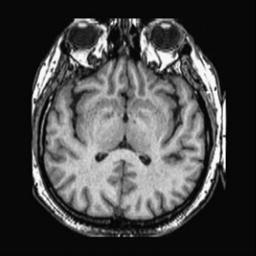

To demonstrate the effectiveness and efficiency of the proposed image fusion method , we conduct a set of comparative experiments on three image datasets. The first is composed by 8 pairs of multi-modal medical images and the second one contains 15 pairs of multi-focus gray or color natural images. These two datasets are often used in many related papers and some examples are shown in Figure 3(a) and Figure 3(b). The third one is a new multi-focus cervical cell image dataset collected by ourselves, which consists of 15 groups of color images and each group contains a series of multi-focus cervix cell images with size of or , etc. Some source examples are shown in Figure 3(c). Our source code implemented in C++ along with the new multi-focus cervical cell image dataset is available online.

We first evaluate the performance of the proposed method under varying total number of octaves and number of layers sampled per octave. The fused images of a pair of multi-modal medical images with different and are shown in Figure 4. In this example, on the one hand, when only 1 or 2 octaves are involved in constructing the DoG pyramid, the fused images fail to keep the integrity information of large size objects (e.g. eyeballs), while by increasing the value of , the integrity information of eyeballs is preserved. On the other hand, although not as significant as the increase of octave numbers , the fused image can contain more details by the increase of layer numbers . The corresponding objective quality metrics are shown in Figure 5. As shown in Figure 5(a), most of the metric values are improved as the number of octaves increases with the fixed layer numbers 3 in the global tendency and each of them tends to be stable when the number of octaves is 5. To get a relatively good quality from Figure 5(b), we can notice that some of the metric values can get a good performance when the number of layers is 3, such as the MI, SSIM, QI and VIF, though there are only a little change of all the metric values by increasing the number of layers with the fixed octave numbers 5. Because it will result in more computation burden with the increase of the value and , and for different kinds of source images, there are different performance with the diverse parameter settings. To get a trade-off between them in our experiments, we set for the multi-modal dataset, for the natural datasets and for the multi-focus cell dataset, respectively.

Figure 6 shows the fused images obtained by different methods with the multi-modal source images shown in Figure 3(a). As shown in these figures, the proposed method can produce images which preserve the complementary information of different source images well. Moreover, due to the scale-invariant structure saliency selection, our method can keep the integrity information of large size objects and the visual details simultaneously. Although the fused image generated by other methods can also capture the details to some extent, all of them fail to keep the integrity information of large size objects such as the eyeballs. Furthermore, from Figure 6(k)-6(t), the DTCWT, GFF, IM and NSCT methods may decrease the brightness and contrast while the proposed method can preserve these features and details without producing visible artifacts and brightness distortions.